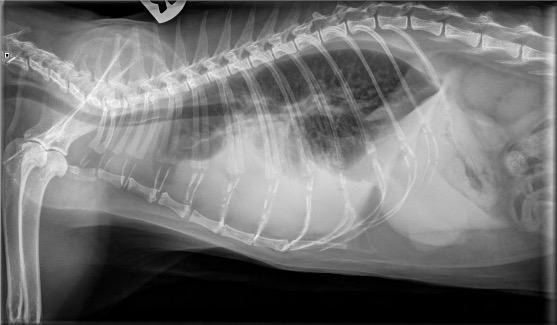

C’est une technique d’imagerie qui utilise les rayons X qui vont imprégner une pellicule comme une photographie et produire une image fixe en 2 dimensions. La radiographie est souvent le premier examen d’imagerie proposé dans les cabinets vétérinaires car c’est un examen rapide d’execution et relativement bon marché. C’est l’examen de prédilection pour l’étude des poumons, mais également la détection de masses, d’urgences médicales comme la torsion d’estomac, l’occlusion intestinale, la présence de corps étranger ou de liquides dans les cavités thoraciques ou abdominales. Les images radiographiques des organes de l’abdomen permettent d’étudier leur silhouette, leur position et leur taille ; mais ne permettent pas d’étudier leur structure interne ou leur fonctionnement.